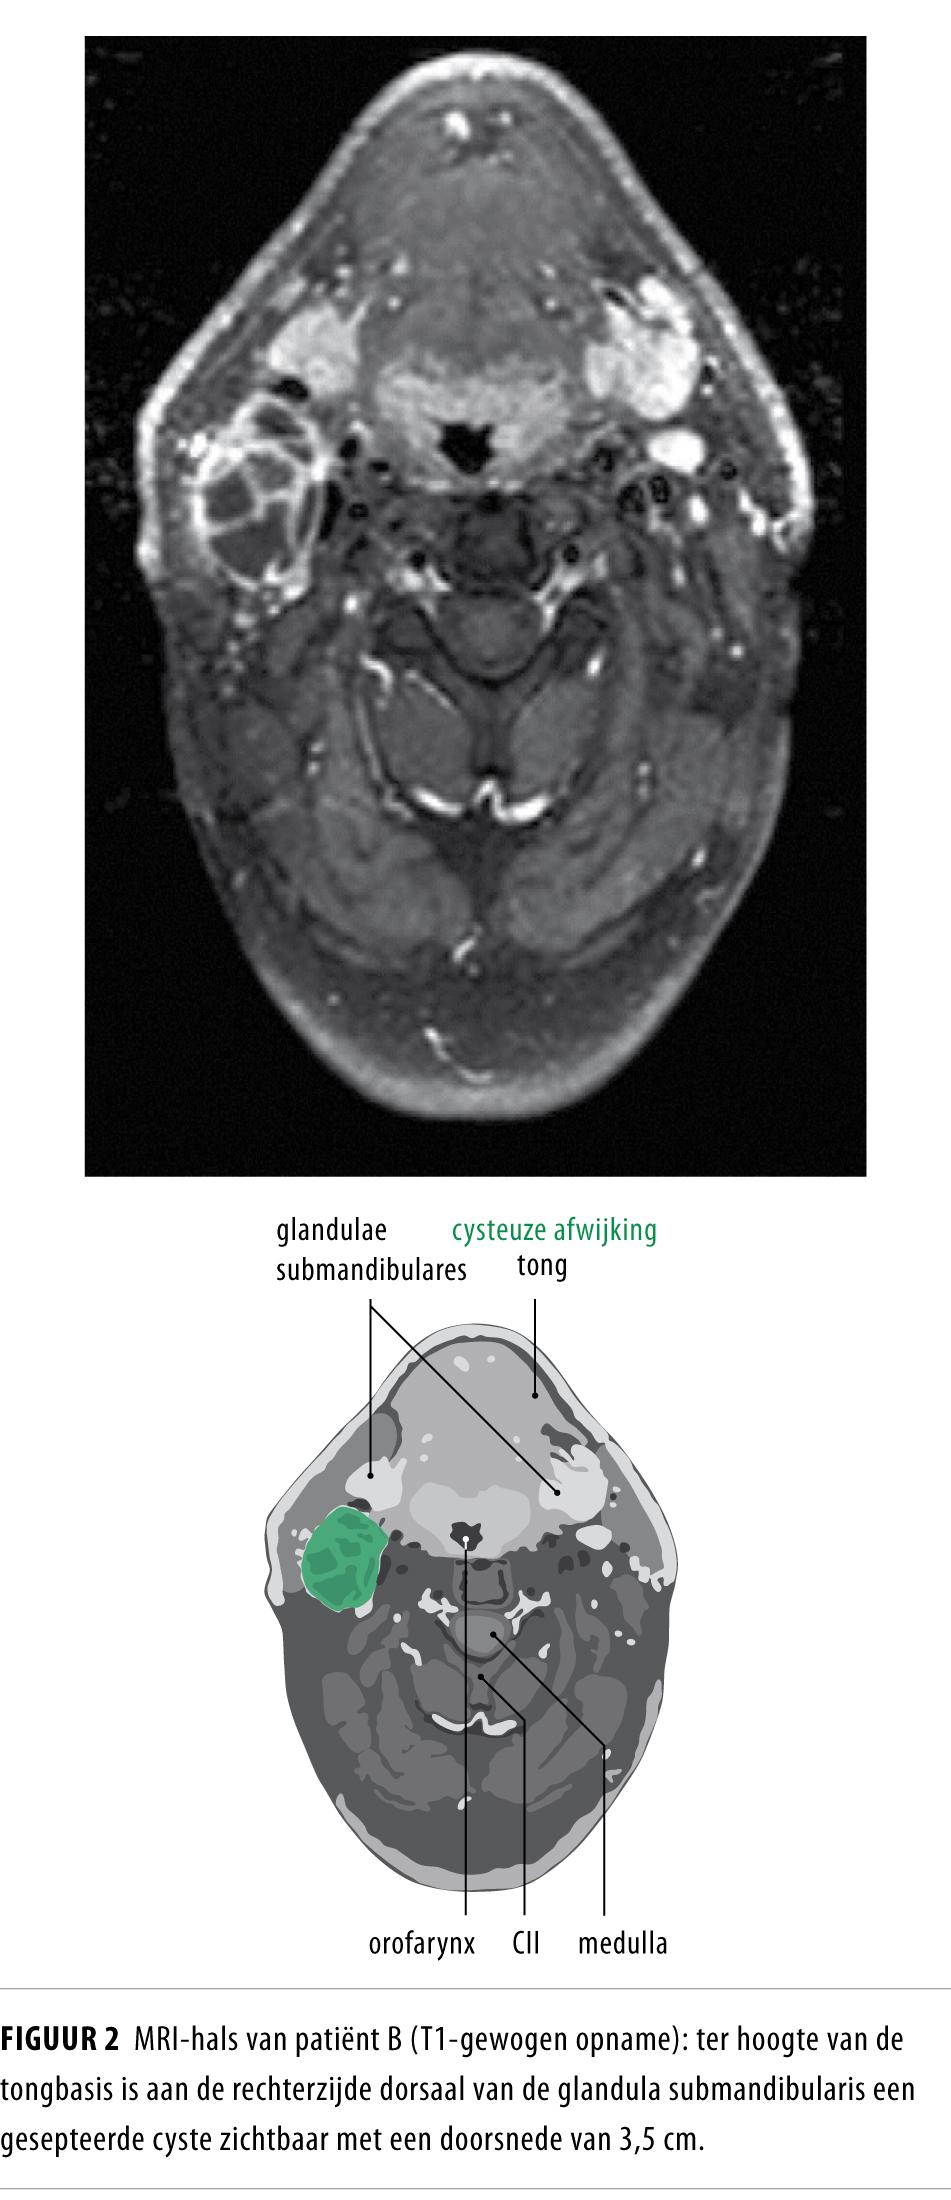

Een cysteuze zwelling in de hals bij volwassen patiënten is meestal een laterale halscyste, maar kan ook een lymfekliermetastase van een primaire tumor in het hoofd-halsgebied zijn. Oplettendheid is met name geboden bij patiënten ouder dan 40 jaar en met risicofactoren als nicotinegebruik en alcoholabusus. Een lymfekliermetastase moet worden uitgesloten voordat de afwijking abusievelijk als laterale halscyste wordt behandeld.

Het is bekend dat lymfekliermetastasen van plaveiselcelcarcinomen uitgaande van de mucosa van de ring van Waldeyer (nasofarynx, tonsillen, tongbasis) een cysteuze verandering kunnen ondergaan en kunnen imponeren als een laterale halscyste.1 De kans dat een cysteuze zwelling in de hals bij patiënten ouder dan 40 jaar berust op een metastase van een hoofd-halstumor is circa 25%.2 In de praktijk blijkt het onderscheid moeilijk.